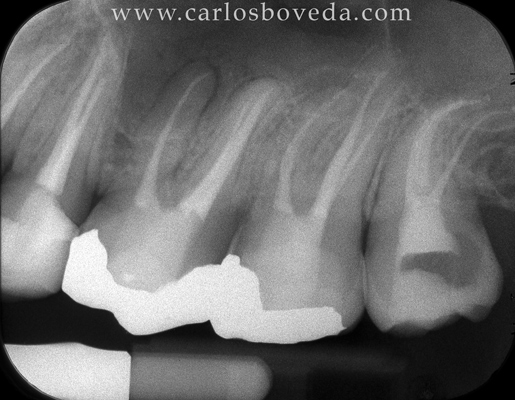

161617